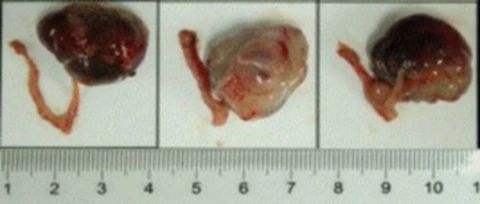

部分beats365PDX原位模型展示

部分beats365PDX原位模型展示